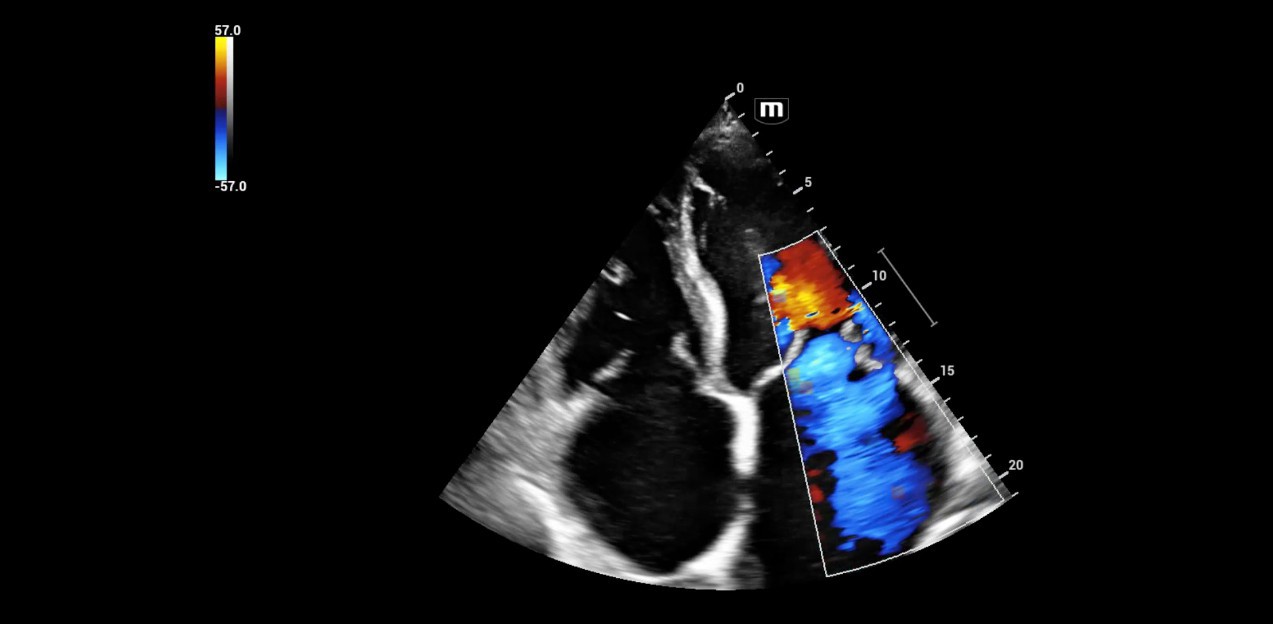

Bestens geeignet sei die Ger?tetechnik auch zur DurchfÞhrung einer trans?sophagealen Echokardiographie (TEE), auch als Schluckecho bekannt. Dabei findet die kardiale Bildgebung Þber eine Ultraschallsonde statt, die in die Speiser?hre eingefÞhrt und bis hinter das Herz geschoben wird. Im intensivmedizinischen Setting nimmt diese Verfahrensweise einen besonderen Stellenwert ein. Denn h?ufig ist ein normaler Herzultraschall gerade bei beatmeten Patienten aus praktischen GrÞnden kaum oder gar nicht m?glich, weil sie fÞr die Untersuchung u. a. nicht optimal positioniert werden k?nnen.